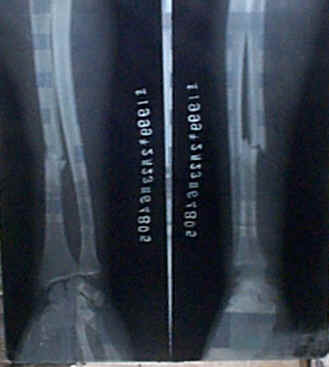

宋文谱,男,汉族,出生于1993年3月7日,住江西省万载县三兴乡红旗10组。1999年4月27日在红旗小学出大门口时被他人自行车撞伤右脚。在万载医院摄片诊断腓骨、胫骨骨裂,由于骑自行车人也是小孩,只赔偿200元。患者因经济不足,没在医院住院,四天后患者被其伯父背来我处治疗。贴一张大号膏药,15天后患者能下地行走,30天自己走去上学。